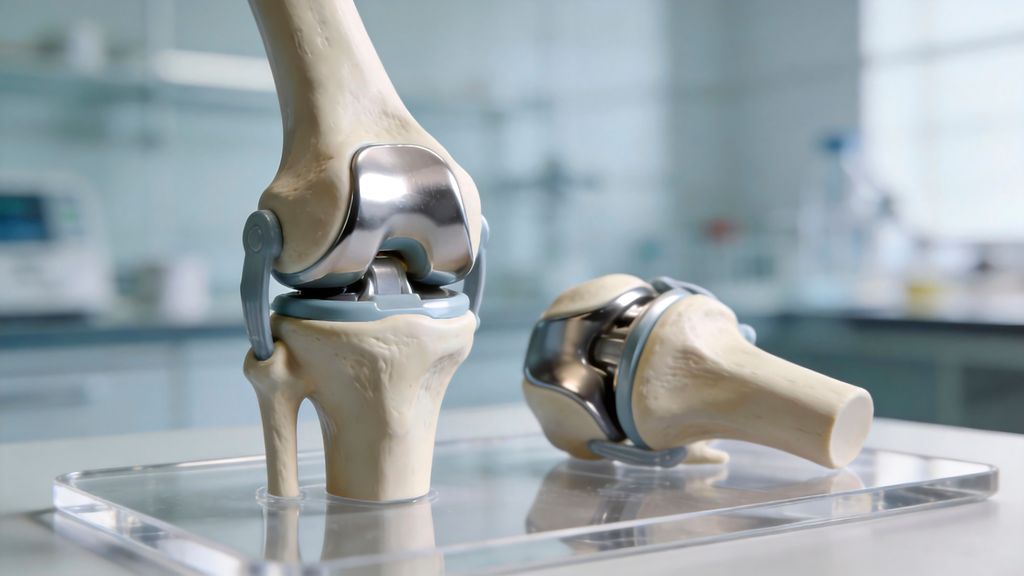

Roboterassistierte primäre Hüfttotalendoprothese – Fortschritt oder Marketing?

Seit der Einführung des RIO®-Systems im Jahr 2006 (MAKO) und der Übernahme durch die Firma Stryker im Jahr 2017 haben nahezu alle grossen Knieendoprothesenhersteller eigene robotische ...